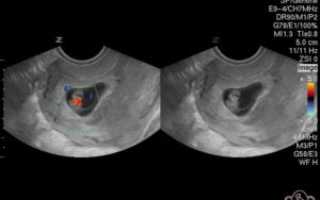

Итак, с шестой недели беременности можно увидеть и измерить биение на экране монитора. Прослушивается сердцебиение плода уже с пятой недели, особенно если УЗ-оборудование имеет хорошую мощность.

Трансвагинальный датчик обнаруживает сердечную деятельность с пятой недели, трансабдоминальный – не ранее, чем с шестой.

Если исследование делать трансвагинальным датчиком, то работу сердца эмбриона можно услышать уже на 5-6 неделе гестации. При проведении трансабдоминального УЗИ обнаружить пульсирующее сердце плода можно на 6-7 неделе. Более достоверная информация о характере и ритме сердцебиения дается трансвагинальным УЗИ.

На шестой акушерской неделе сердечко эмбриона начинает сокращаться. Начиная с этого периода внутриутробного развития эмбриона, становится слышно его сердцебиение на УЗИ.

При помощи данного метода исследования уже на сроке 5 недель видно плодное яйцо, имеющее размеры около 7 мм, и слышно сердечные сокращения, которые составляют примерно 100 ударов за минуту.